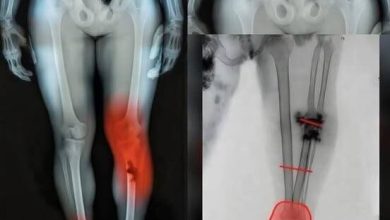

For the clinicians and researchers who have remained in the trenches of pharmacovigilance, the findings are less a shock than a long-awaited clarity. Behind the polished PR lines and the heated political debates, a living archive of data was being quietly compiled. This wasn’t a game of chess played with misinformation; it was a rigorous, multi-national effort to document the rare but serious adverse events that follow mass vaccination. The Global Vaccine Data Network, analyzing records across eight countries, has now brought these “hidden journeys” into the light. From myocarditis and specific clotting disorders to sudden elevations in blood pressure and severe allergic reactions, the study has confirmed that for a small subset of the population, the vaccine came with a personal cost that was neither imagined nor coincidental.

In the early days of the rollout, the urgency of the crisis meant that the messaging was focused on the “shield” of the vaccine. But as time has passed, the “legacy of scars” left by the pandemic has become more visible. The 99-million person study has sharpened the balance for healthcare professionals who must now navigate a landscape of nuanced risk. Recognizing that some people experienced life-altering changes in menstrual patterns or rare neurological events is not an argument against the science of immunization; it is an argument for a more honest, “painfully human” healthcare system. It is a refusal to treat people as mere statistics in a spreadsheet and instead see them as individuals whose “private horror” deserves a public testimony.

The “forensic” belief that we could navigate a global pandemic without any unforeseen consequences was a comforting illusion, but the reality is much more complex. Every medical intervention carries a “map of scars,” and the COVID-19 vaccine is no exception. The study’s findings point to a future where we no longer retreat into absolutes. We can celebrate the millions of lives saved while simultaneously providing “unwavering support” for the few who paid the ultimate price for that success. It is a story of resilience—not just the resilience of the human immune system, but the resilience of a scientific community that is finally brave enough to look at its own data without blinking.